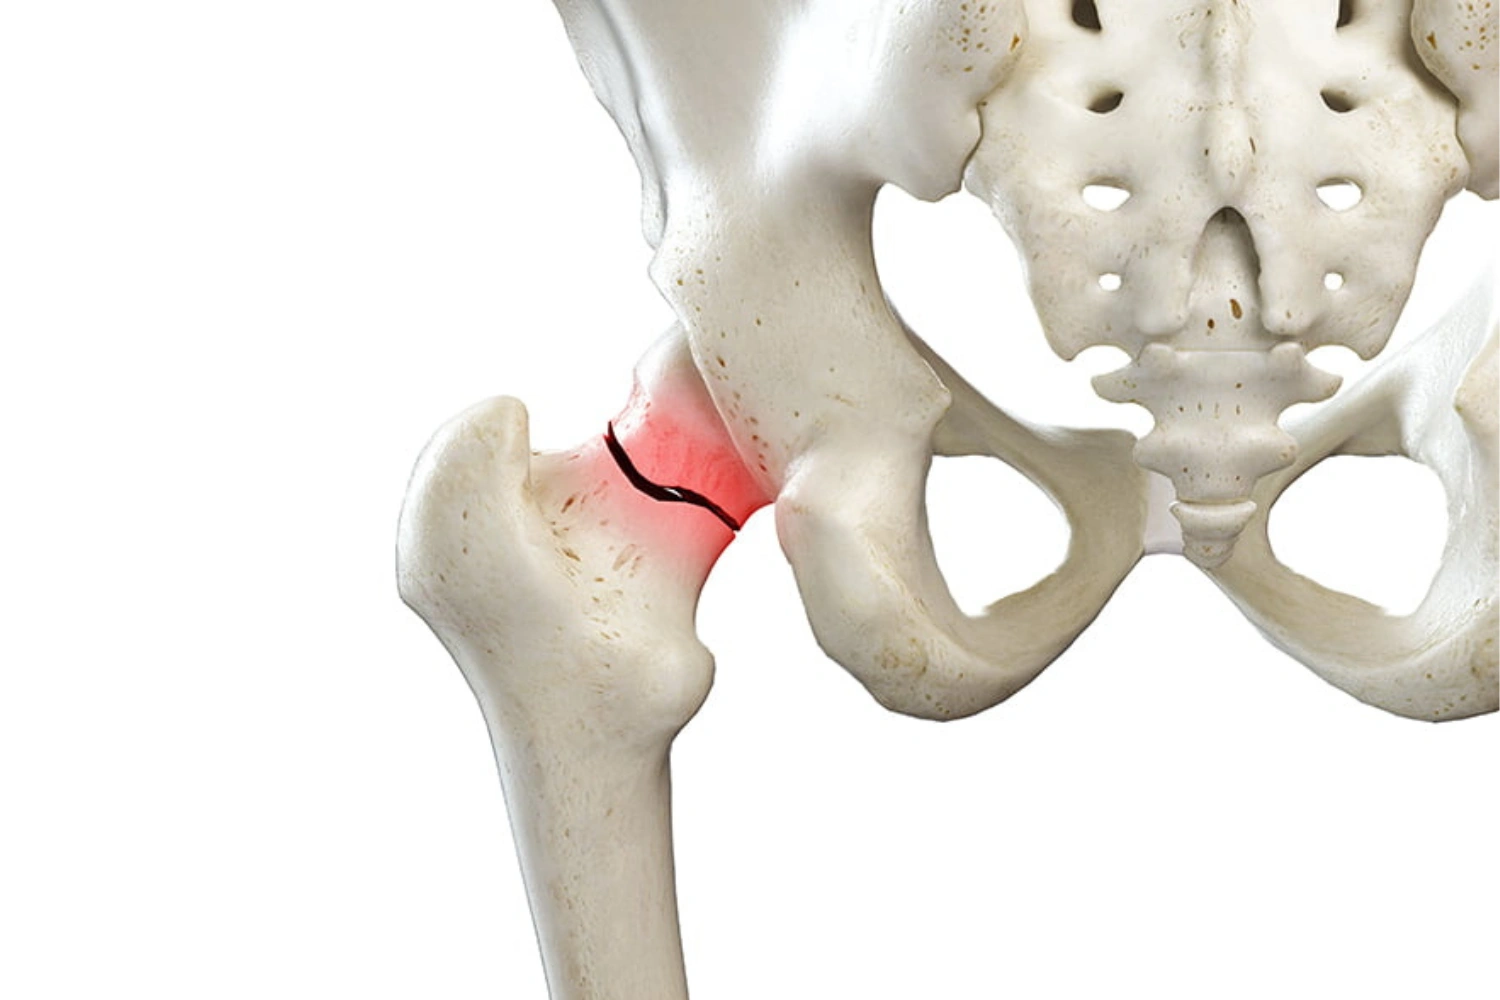

Hip Fractures